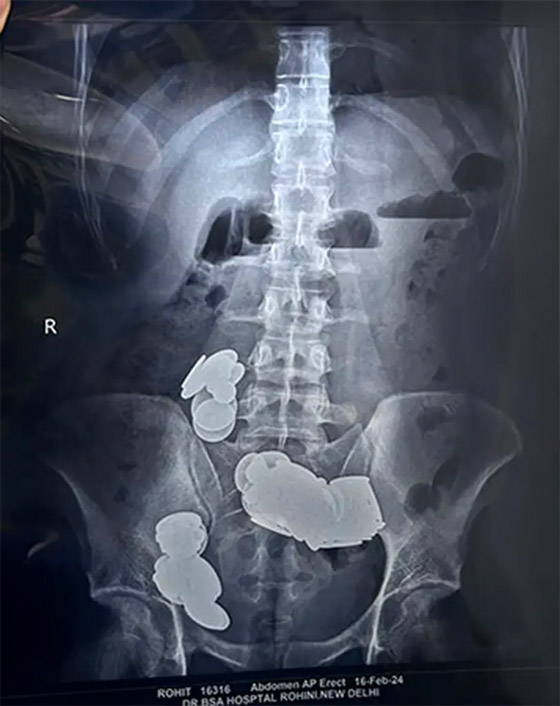

Share

لاعتقادات غريبة، ابتلع شاب قطعا معدنية وعددا من المغناطيس، بما آل به إلى معاناته من أضرار صحية بالغة. وفوجئ أطباء مستشفى "سير جانجا رام" في مدينة نيودلهي الهندية، باستقبال شاب في قسم الطوارئ يبلغ من العُمر 26 عاما، يعاني من اسنداد معوي. واكتشف الأطباء أن أمعاء الشاب بها 37 مغناطيسًا و39 عملة معدنية، بعد إجراء الأشعة السينية، ما ناتهى إلى إصابته بانسداد في الأمعاء. وفوجئ الأطباء بالشاب وهو يعاني من حالة قيء، كما اكتشفوا أنه يعاني من ألم دائم لـ20 يوما متتاليا.

وأفادت تقارير محلية بأن الشاب ابتلع هذه القطع ظنا منه بانها ستساعد جسده على امتصاص الزنك، ومن ثم سيحظى بجسم رياضي يضاهي لاعبي كمال الأجسام. كما كشفت التقارير أن الشاب ابتلع هذه القطع أثناء علاجه من حالة نفسية، لم كشف عنها. وبعد إجراء الفحوصات الأولية، خضع الشاب لعملية جراحية، لاستخراج جميع القطع التي ابتلعها.